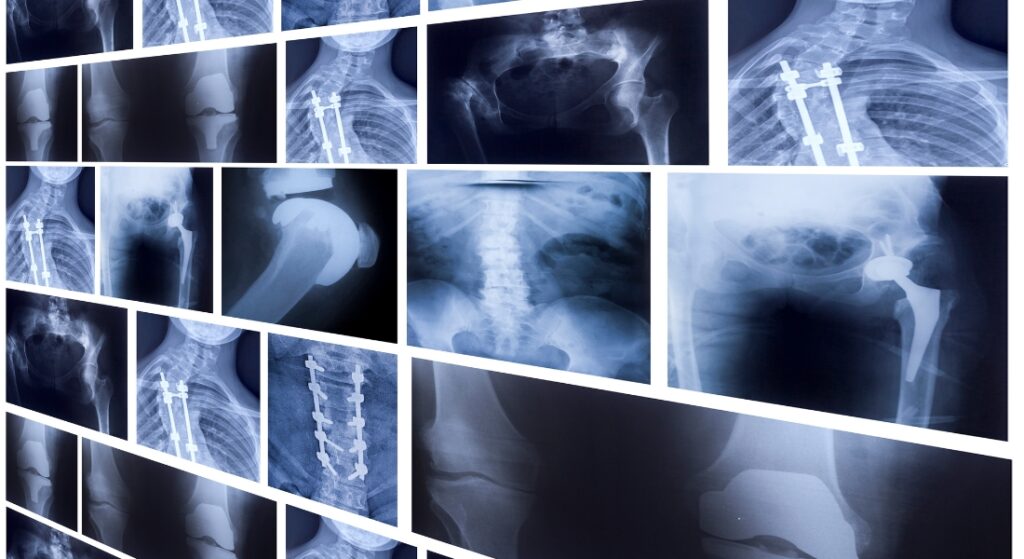

Các loại chụp X-quang thường gặp

Chụp X-quang được ứng dụng rộng rãi ở nhiều chuyên khoa, tùy từng vị trí và mục đích:

Chụp X-quang xương khớp

- Chẩn đoán gãy xương, trật khớp (cổ tay, cổ chân, vai, đùi, cột sống).

- Phát hiện các bệnh mạn tính: loãng xương (hình ảnh xương mờ, mất vỏ xương), thoái hóa khớp (hẹp khe khớp, gai xương).

- Đánh giá sau phẫu thuật kết hợp xương, theo dõi tiến triển xương liền hay không.

Chụp X-quang phổi

- Phát hiện các dấu hiệu viêm phổi (đám mờ, đông đặc), lao phổi (hang, xơ hóa), u phổi, tràn dịch màng phổi (mờ đều góc sườn hoành, hình ảnh mức nước khí).

- Theo dõi tiến triển sau điều trị, kiểm tra di căn ở bệnh nhân ung thư.

Chụp X-quang răng – hàm – mặt

- Đánh giá cấu trúc xương hàm, phát hiện răng khôn mọc lệch, viêm xương hàm, sâu răng, áp xe quanh răng.

- Chụp toàn cảnh (panorama) hoặc phim cận chóp giúp nha sĩ lập kế hoạch điều trị chính xác.

Chụp X-quang bụng

- Phát hiện tắc ruột (hình ảnh mức nước – mức khí), sỏi tiết niệu (hình ảnh cản quang đường tiểu), khối u hoặc dị vật ổ bụng.

- Đánh giá tình trạng bụng cấp trong cấp cứu ngoại khoa.